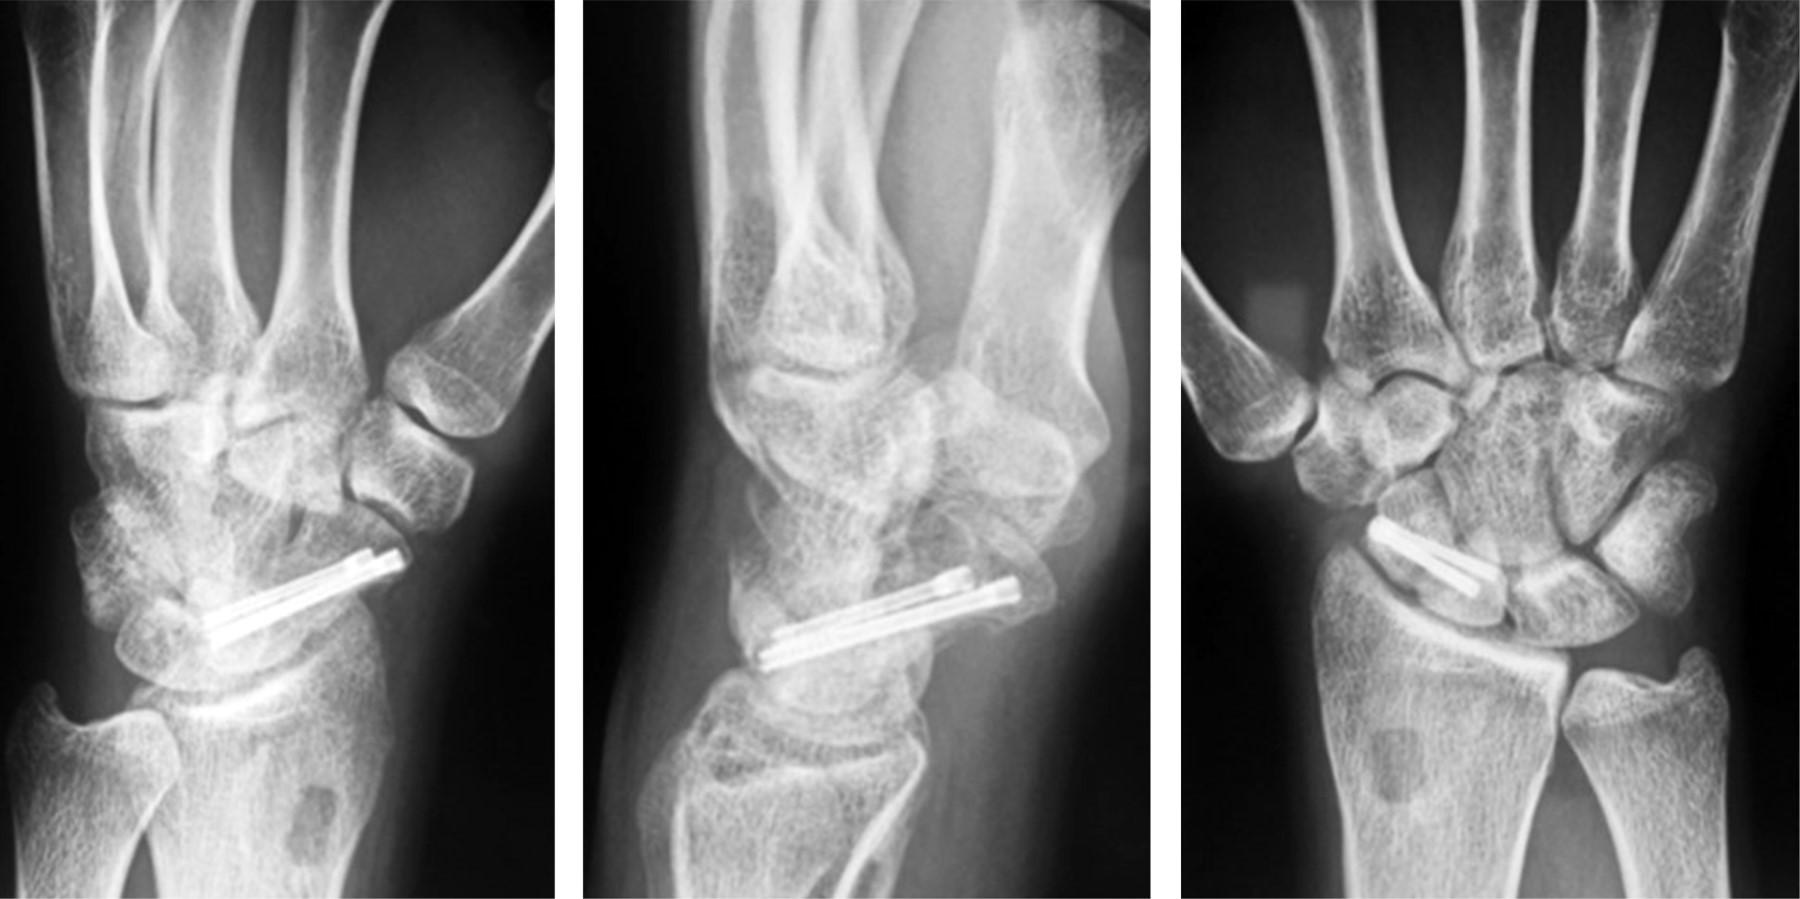

Una vez obtenida la reducción se perforó con dos clavillos Kirschner desde el polo distal y desde tubérculo escafoídeo hacia el polo proximal, perpendicular al trazo de fractura. Se brocó a través de guía y se colocó autoinjerto óseo esponjoso de radio distal en el defecto para después introducir los tornillos canulados sin cabeza bajo visión fluoroscópica (Figura 3).

Se corrigió la deformidad en joroba del escafoides que mostraban los dos pacientes y se corrigió la inestabilidad dorsal del segmento intercalado en dos de los tres pacientes que lo presentaban (Figura 4).

Figura 3

Figura 4